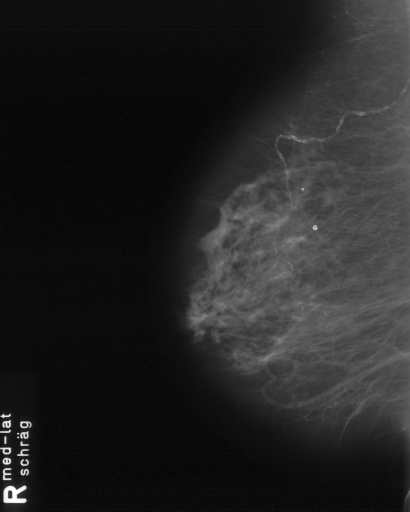

In this series of experiments, we randomly selected three categories from IRMA dataset (namely, breast, foot and lung), and for each category we choose 5 random images from that class (Figures 5, 6 and 7 show these images). When we find “4 out of 180” (4/180) and “8 out of 180” (8/180) projections via micro-DE (tasks that cannot be performed via brute-force), then the question is what can we say about the reconstruction error, in terms of correlation between original and reconstructed images, when we compare evolutionary approximation with the case that we can manage via exhaustive search, namely “4 out of 16” (4/16)? Can micro-DE reach at least the same correlation (similarity) as the brute-force case in lower dimensions? If yes, we may have more confidence in using micro-DE in practice where we cannot apply brute force for benchmarking or direct use, especially for higher dimensions (i.e., the number of projections).

For finding optimal projections based on micro-DE (4 out of 180), we set the parameters of micro-DE to be NFC, , , , and we run each experiment 30 times. For optimal projections based on micro-DE (8 out of 180), we set NFC, , , , and we run each experiment 30 times. The results are presented in Tables 2, 3 and 4. In all cases, micro-DE (MDE) with 4/180 reaches the same correlations as brute force (BF) for 4/16. Of course, MDE finds different projections as it is searching the entire search space of . However, that the same level of reconstruction accuracy can be achieved establishes the reliability of MDE as a practical solution that may even produce a higher-level of uniqueness for Radon barcodes as 4 projections are selected among all 180 angles (the increased uniqueness needs to be verified by applying the Radon barcodes for image retrieval). On the other hand, MDE for 8/180 clearly increases the correlation with statistical significance. This is very encouraging as we can generate more expressive Radon barcodes using a higher number of projections.

| image | BF (4/16) | MDE (4/180) | MDE (8/180) | |||

|---|---|---|---|---|---|---|

| f1 | [34,67,112,157] | 0.79 | [30,80,110,150] | 0.80 | [80,160,30,130,30,100,140,60] | 0.85 |

| f2 | [79,101,135,169] | 0.73 | [80,110,140,170] | 0.73 | [70,20,160,0,120,80,130,100] | 0.80 |

| f3 | [11,56,112,158] | 0.64 | [20,60,100,170] | 0.65 | [40,130,160,70,10,170,110,60] | 0.70 |

| f4 | [11,79,101,169] | 0.77 | [0,30,80,100] | 0.77 | [20,180,50,60,80,110,170,120] | 0.84 |

| f5 | [22,67,112,157] | 0.85 | [80,30,120,160] | 0.86 | [120,60,80,10,150,100,170,40] | 0.89 |